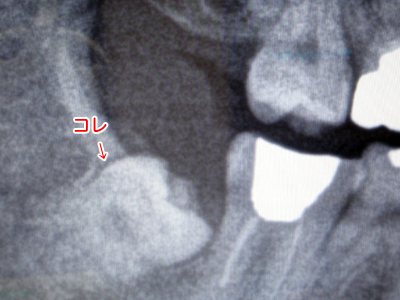

それよりも更に気がかりなのが左下の親不知である。今回のレントゲンで明らかになったのだが、嫌な角度で生えているのだ。これを抜くのはちょっと大変らしい。ああ、困った。

嫌な生え方をしている